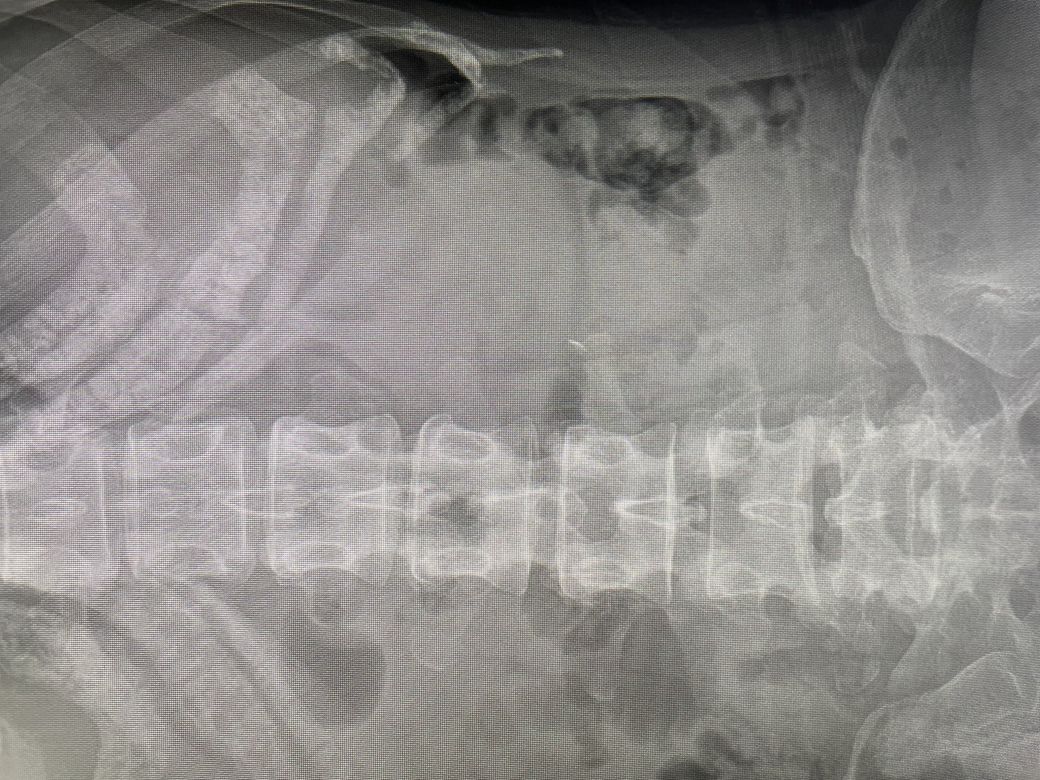

병원에서 엑스레이를 찍었는데

철심으로 의심되보인다고 하셨습니다.

엑스레이에 보이는 이물질이 철심이 맞을까요..

현재 사진만으로는 정확한 구분이 어렵습니다. 척추 뼈 옆쪽 이물질로 추정되는 물체가 보이기는 하지만 길이가 조금 짧아 보이며 이는 엑스레이가 2차원적인 촬영으로 인한 착시일 수 있습니다. 그러므로 상급병원 외과와 협진이 가능한 곳으로 내원하시어 복부 CT등을 촬영하시고 필요하다면 수술이 필요할 수도 있겠습니다.

철심이 복부에 존재하는 것으로 보입니다. 정황상으로도 맞는 것으로 생각됩니다.

금속은 엑스레이에서 표시가 됩니다. 일단 통증이 있는 부위에 발견된 금속이라면 질문자분 말씀하신 대로 와이어가 떨어진 것이 장에 있을 가능성이 있습니다. 보통은 큰 문제 없이 변으로 배출이 되겠지만 심한 복통 및 금속의 이동이 없다면 외과 전문의에게 진료를 보시고 제거가 필요할수도 있습니다.

2.5cm 짜리 철사인 경우 길이가 많이 길지는 않아(<5cm) 배출까지 한달까지는 기다려볼수 있지만

현재 4개월이 지난 시점에서도 배출이 되지 않는다면 외과적인 개입이 필요할 수도 있습니다.

현재 내시경적인 제거는 십이지장 정도까지 위치해있을때 가능하나 그 위치를 넘어가 보이며

다시 한번 x-ray 및 CT 촬영을 하고 정확한 위치 확인 뒤에 일반외과 진료를 보셔서 제거 상담을 해보셔야 할것 같습니다.

현재 사진상으로 보면 오른쪽 복부 내부에 정말 조그마한 하얀색 음영이 보이기는 합니다.

이물질이 맞다면 소장위치로 보입니다. 일반 상부 내시경은 위, 대장 내시경은 대장만 접근이 가능하기 때문에 철심을 제거할 방법에 대한 진료를 보시는게 맞겠습니다.